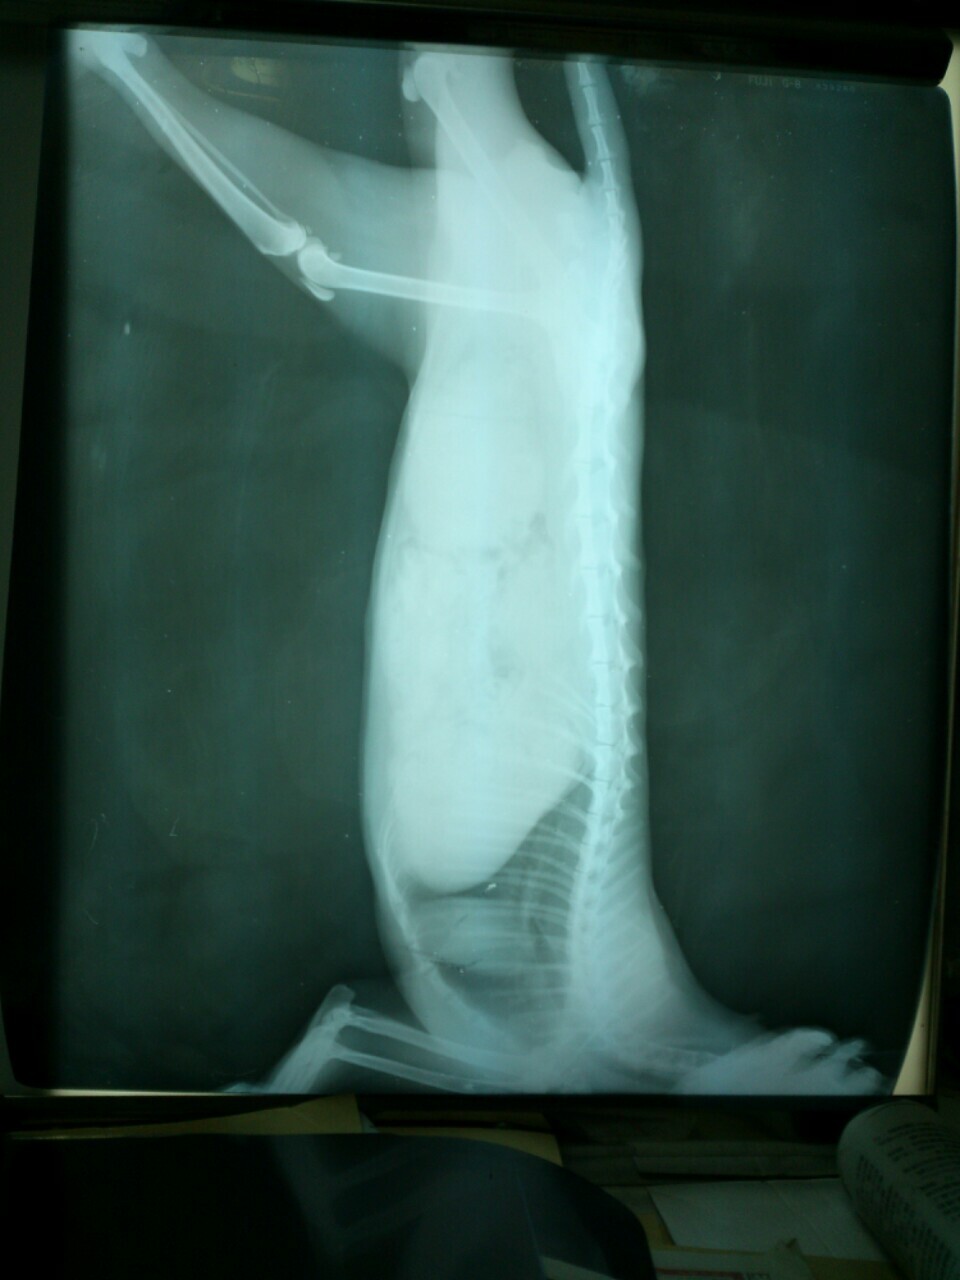

1/19貓咪照X光,確定為骨盆腔錯位碎裂,癱瘓機率非常高!

只能等待骨盆腔骨頭自行慢慢癒合之後再評估做後續醫療,

貓咪無法自行排尿,需要每天早、中、晚幫貓咪擠尿。(可以自行排便)